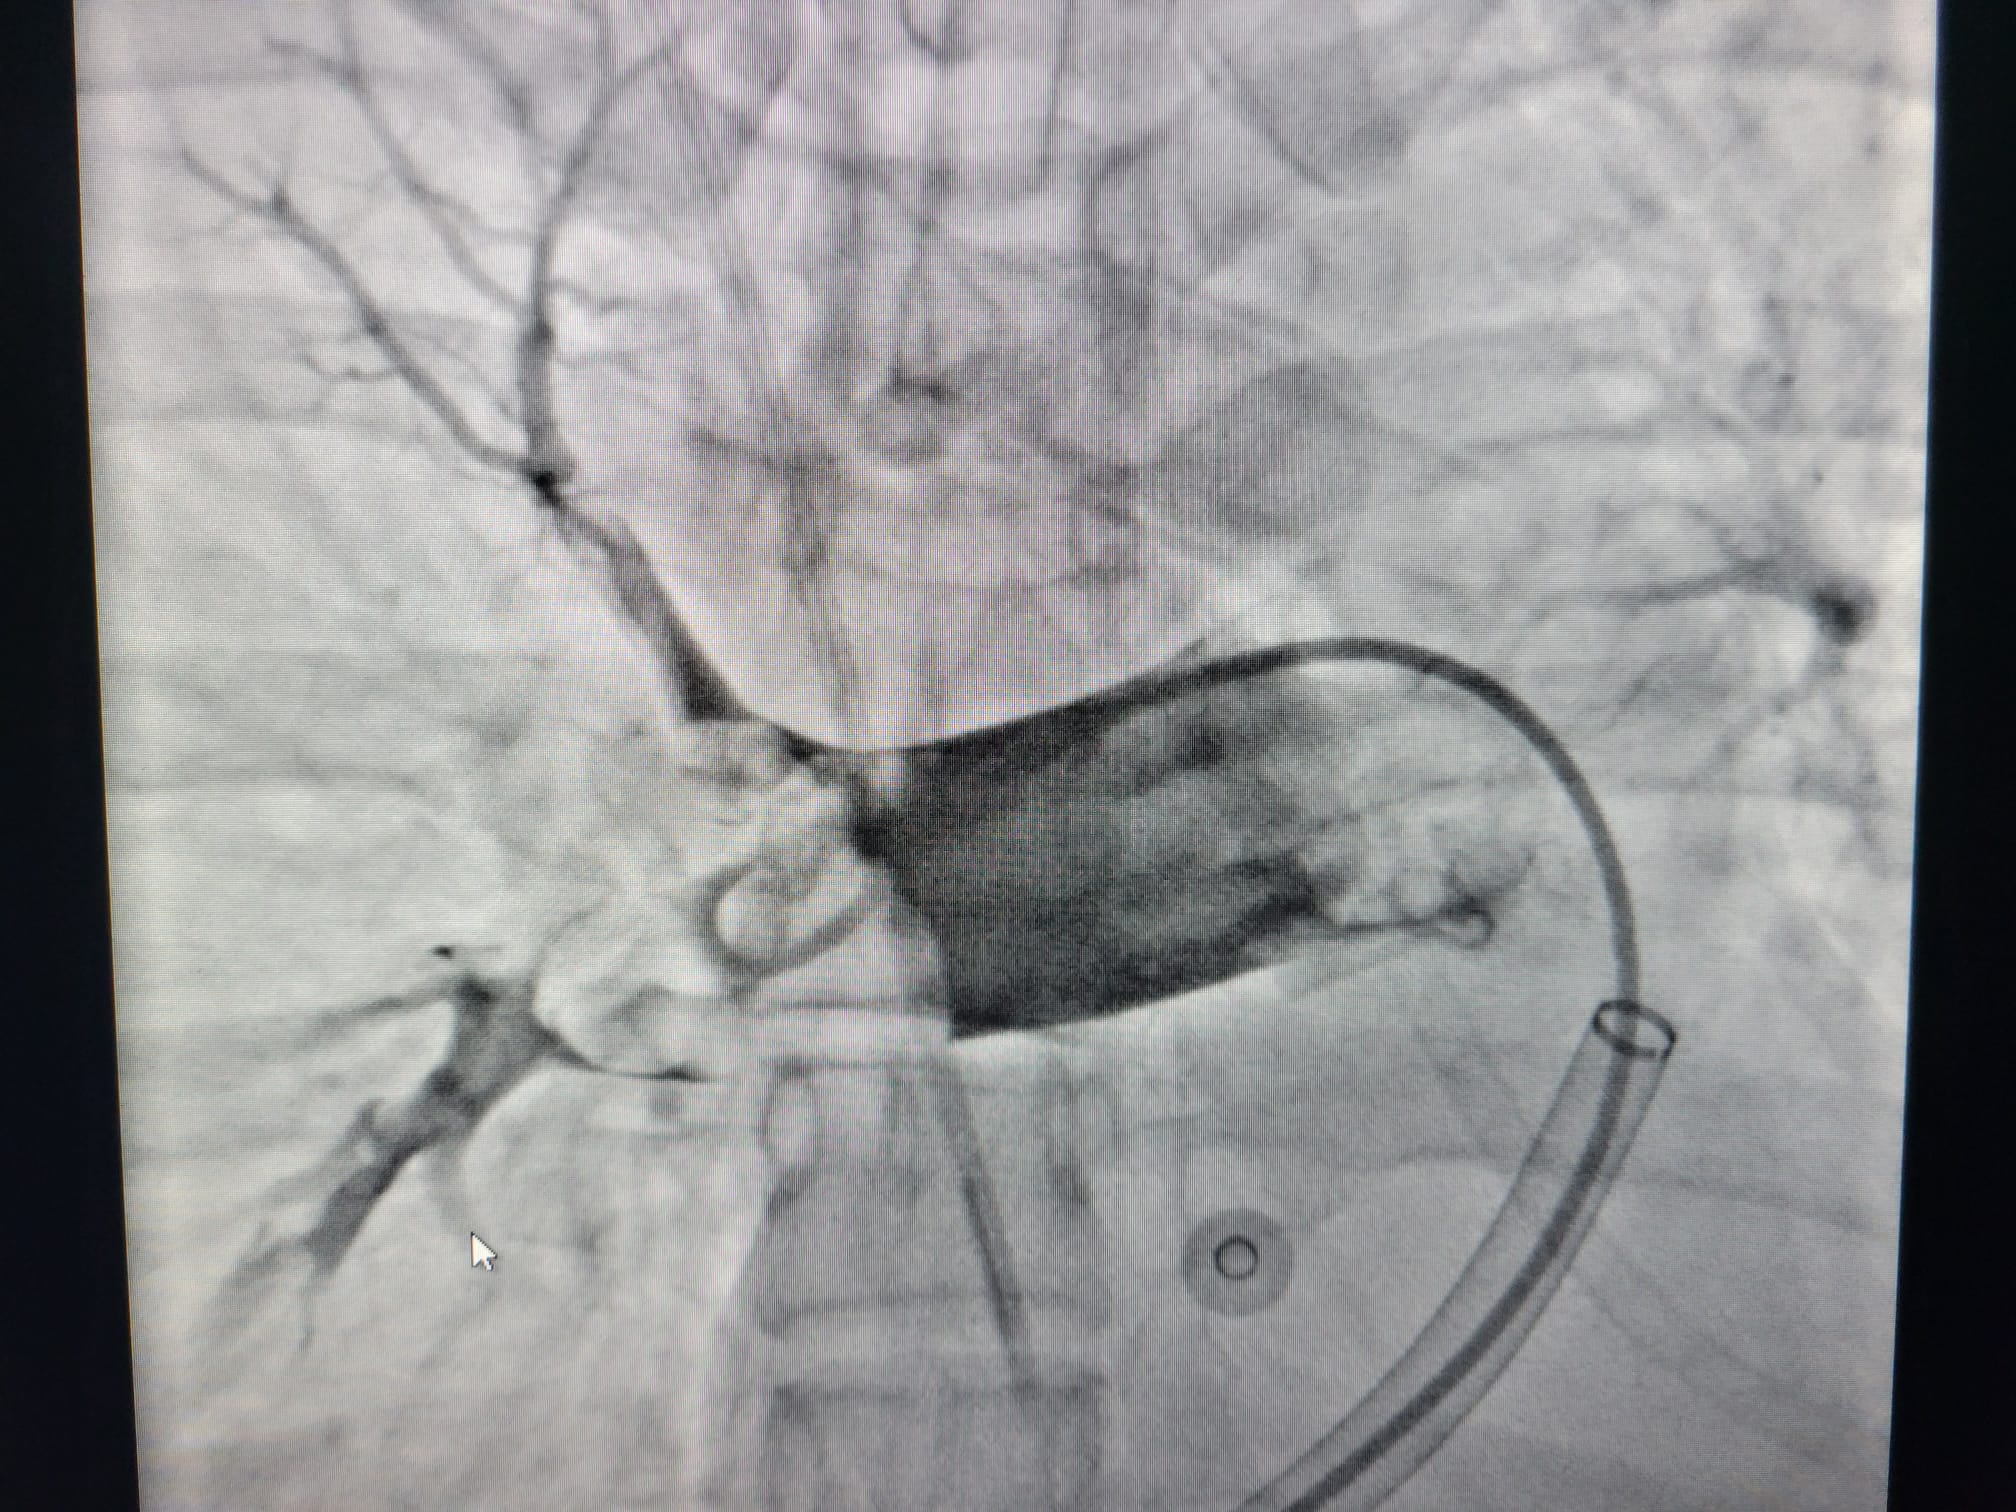

Više o ovoj bolesti otkrila su nam trojica mladih interventnih kardiologa, dr. Nikola Crnčević, dr. Velimir Pivac i dr. sc. Dino Mirić, sa Klinike za bolesti srca i krvnih žila Kliničkog bolničkog centra Split, koji su započeli s tromboaspiracijom, novom metodom liječenja najugroženijih pacijenata s klinički nestabilnom embolijom pluća, u kojih nije preporučena ili je zabranjena primjena fibrinolitičke terapije.